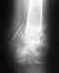

Вот я и сходил к травматологу в поликлинику. Радует, что хоть снимки теперь на руках, можно выложить, что собственно я и сделал. Снимал фотиком, так что если что не разобрать - постараюсь лучше сделать. Скажите, какие дальнейшие действия по нагрузке ноги? А то информации практически нет. Врач принимал другой, не тот что карту мою составлял. Этот только сделал снимок и записал на дальнейший прием в первому врачу. Врач, который проводил операцию, сейчас в отпуске. В больнице травматологи сказали, что можно давать нагрузку, разрабатывать ногу, но потихоньку, и очень аккуратно, а то колено после 2-х месяцев слабое. Оно в действительности, так и есть. Но на двух ногах я уже после 7 недели стоял. только ходил на одной ноге с костылями. Щас пытаюсь ходить с одним костылем, который просто в руке держится. Колено хоть и держит при опоре на костыль, но не долго. Где-то 1-2 секунды. Потом начинает слабеть и болеть. В принципе, чтобы сделать шаг, хватает. Но вот подняться на ступеньку (они пока еще есть в совдеповских квартирах) это сложно. Поэтому в другой руке ношу обычный деревянный костыль.

Отсюда вопрос... Какая нагрузка на ногу возможна при таком состоянии, как на снимках? Колено ведь у человека способно держать очень большую нагрузку. но ведь есть же какие-то ограничения в связи с переломом? После того, как восстановится колено, можно ли будет ходить без костылей, просто хромая на одну ногу? Или до полного сращения не стоит?

Вы так и не указали дату операции. Предполагаю, что прошло больше 2 мес.

На снимках все хорошо.

Нагрузка возможна та, которая получается без хромоты. Т.е. если можете идти, не хромая, без костылей и трости - на здоровье. Если сильно хромаете - пользуйтесь дополнительной опорой в противоположной руке. Движения в колене надо уже разработать, уже должны свободно садиться на корточки.

Колено не бывает "слабое", слабые могут быть только мышцы. Давайте им нагрузку - поднимайте прямую ногу, разгибайте колено, преодолевая сопротивление.

Да, вы правы, снимок сделан на 10-й неделе (после 2 мес.). Вот только выкладывал еще при выписке снимки, с комментариями на изображении. Видать, было отредактировано. Ну хоть эти остались... и ладно...

Ходить с тростью с каждым днем получается все лучше. И в плане равновессия моего, и в плане колена. Но дальше квартиры пока боюсь. Уже колено болит меньше, но полную нагрузку пока не выдержит. А вот на корточки сесть не получиться. К 8 неделе уже нога дальше чем на 90 градусов не сгибалась. Если пытаться и дальше согнуть - появляются боли в самом конце бедра в районе колена. Там еще через кожу можно нащупать заостренный конец болта. Сначала думал на этот болт, но в больнице сказали, что раньше чем через год об этом разговора быть не может. Так что пока разрабатываю колено, может и лучше будет... Выложил опять снимок, там болты лучше видно. Скажите, это нормально болт установлен?